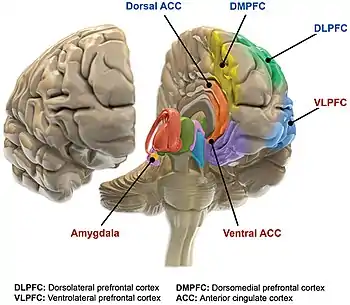

Bipolar disorder is an affective disorder characterized by periods of elevated and depressed mood. The cause and mechanism of bipolar disorder is not yet known, and the study of its biological origins is ongoing. Although no single gene causes the disorder, a number of genes are linked to increase risk of the disorder, and various gene environment interactions may play a role in predisposing individuals to developing bipolar disorder. Neuroimaging and postmortem studies have found abnormalities in a variety of brain regions, and most commonly implicated regions include the ventral prefrontal cortex and amygdala. Dysfunction in emotional circuits located in these regions have been hypothesized as a mechanism for bipolar disorder.[1] A number of lines of evidence suggests abnormalities in neurotransmission, intracellular signalling, and cellular functioning as possibly playing a role in bipolar disorder.[2]

The main loci of neuroimaging and neuropathological findings in bipolar have been proposed to constitute dysfunction in a "visceromotor" network, composed of the medial prefrontal cortex (mPFC), anterior cingulate cortex (ACC), orbitofrontal cortex (OFC), hippocampus, amygdala, hypothalamus, striatum and thalamus.[32]

A model of functional neuroanatomy produced by a workgroup led by Stephen M. Strakowski concluded that bipolar was characterized by reduced connectivity, due to abnormal pruning or development, in the prefrontal-striatal-pallidal-thalamic-limbic network leading to dysregulated emotional responses. This model was supported by a number of common neuroimaging findings. Dysregulation of limbic structures is evinced by the fact that hyperactivity in the amygdala in response to facial stimuli has been consistently reported in mania.[33] While amygdala hyperactivity is not a uniform finding, a number of methodological challenges could explain discrepancies. As most studies utilize fMRI to measure blood-oxygen-level dependent signal, excess baseline activity could result in null findings due to subtraction analysis. Furthermore, heterogenous study design could mask consistent hyperactivity to specific stimuli. Regardless of directionality of amygdala abnormalities, as the amygdala plays a central role in emotional systems, these findings support dysfunctional emotional circuits in bipolar. A general reduction in ventrolateral prefrontal cortex activity is observed in bipolar, and is lateralized with regard to mood (i.e., left-depression, right-mania), and may underlie amygdala abnormalities. The dorsal ACC is commonly under-activated in bipolar, and is generally implicated in cognitive functions, while the ventral ACC is hyperactive and implicated in emotional functions. Combined, these abnormalities support the prefrontal-striatal-pallidial-thalamic limbic network underlying dysfunction in emotional regulation in bipolar disorder.[34] Strakowski, along with DelBello and Adler have put forward a model of "anterior limbic" dysfunction in bipolar disorder in a number of papers.[35][36][37][38][39]

Green at al 2007 suggested a model of bipolar disorder based on the convergence of cognitive and emotional processing on certain structures. For example, the dACC and sgACC were cognitively associated with impairment of inhibition of emotional responses and self monitoring, which could translate to emotional stimuli having excessive impact on mood. Deficits in working memory associated with abnormal dlPFC function could also translate to impaired ability to represent emotional stimuli, and therefore the impaired ability to reappraise emotional stimuli. Dysfunction in the amygdala and striatum has been associated with attentional biases, and may represent a bottom up mechanism of dysfunctional emotional processing.[40]

Blond et al. proposed a model centered on dysfunction in an "amygdala-anterior paralimbic" system. This model was based on the consistent functional and structural abnormalities in the ventral prefrontal cortex and amygdala. The model also proposes a developmental component of bipolar disorder, wherein limbic abnormalities are present early on, but rostral prefrontal abnormalities develop later in the course. The importance of limbic dysfunction early in development is highlighted by the observation that amygdala lesions early in adulthood produce emotional abnormalities that are not present in people who develop amygdala damage in adulthood.[41]

John O. Brooks III put forward a model of bipolar disorder involving dysregulation of a circuit called the "corticolimbic system". The model was based on more or less consistent observations of reduced activity in the medial orbitofrontal cortex, vlPFC, and dlPFC, as well as the more or less consistent observations of increased activity in the amygdala, parahippocampal gyrus, cerebellar vermis, anterior temporal cortex, sgACC, and ACC. This pattern of abnormal activity was suggested to contribute to disrupted cognitive and affective processes in bipolar disorder.[44]

In a review of structural neuroimaging in bipolar disorder, Strakowski proposed dysfunction in an iterative emotional network called the "anterior limbic network", composed of the thalamus, globus pallidus, striatum, ventrolateral prefrontal cortex, ventromedial prefrontal cortex, ACC, amygdala, dorsolateral prefrontal cortex, and cerebellar vermis. Structural imaging studies frequently find abnormalities in these regions which are putatively involved in emotional and cognitive functions that are disrupted in bipolar disorder. For example, while structural neuroimaging studies do not always find abnormal PFC volume in bipolar disorder, when they do, PFC volume is reduced. Furthermore, reduced PFC volume is associated with response inhibition deficits and duration of illness. When the PFC at large is not examined and the focus is narrowed to the orbitofrontal cortex and medial prefrontal cortex, results more consistently observed reductions, although not in bipolar youth. The sgACC volume is observed to be reduced not only in bipolar disorder, but also in unipolar disorder, as well as people with a family history of affective disorders. Enlargement of the striatum and globus pallidus are commonly found, and although some studies fail to observe this, at least one study has reported no volumetric but subtle morphometric abnormalities.[39]